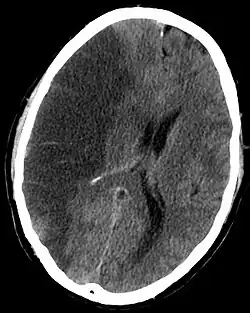

| Uma fatia do cérebro de uma pessoa que foi vítima de um AVC da artéria cerebral média | |